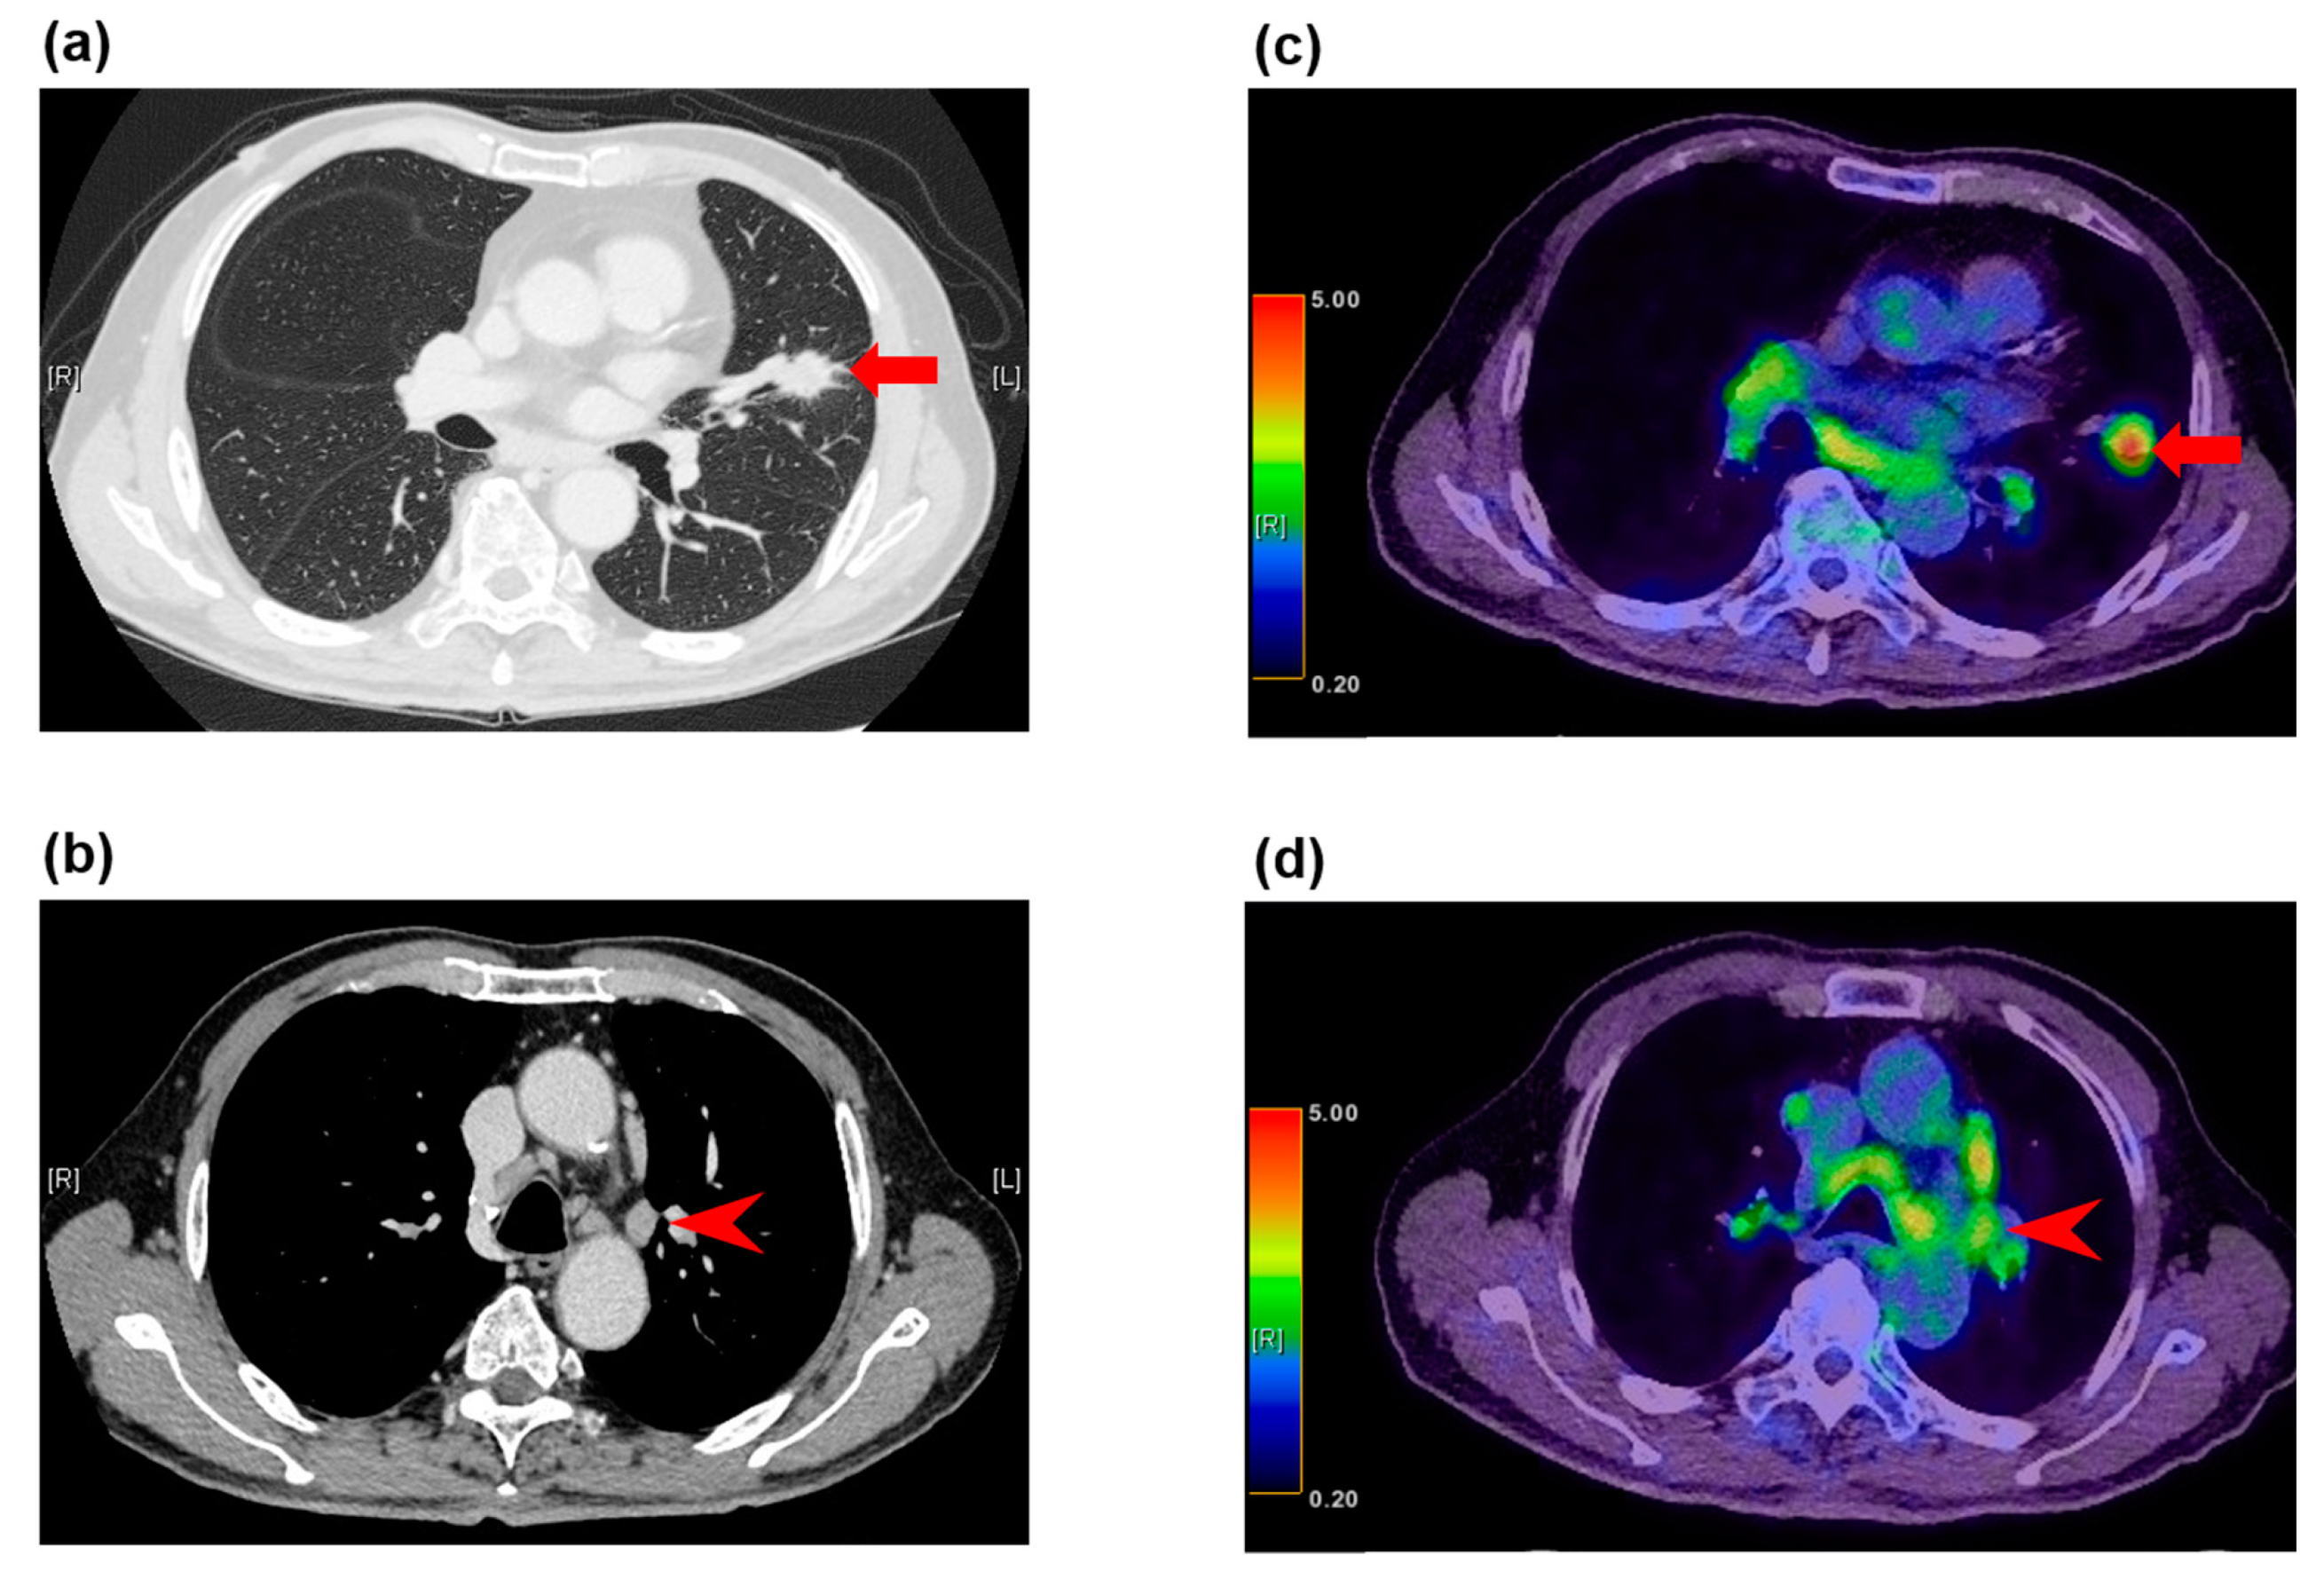

PSMA PET-CT Accurately Detects Prostate Cancer Spread - NCI PET Scan: What It Is, Types, Purpose, Procedure & Results PET/MRI biomarkers guide personalized treatment for patients with pancreatic cancer - Mayo Clinic News Network PSMA-PET is rapidly changing the standard of care for prostate cancer patients | Pet Scan Cancer